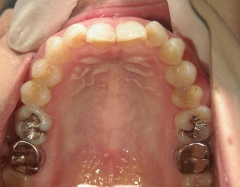

矯正歯科 治療前

36歳女性 磐田市

在住

治療期間2年6

ヶ月